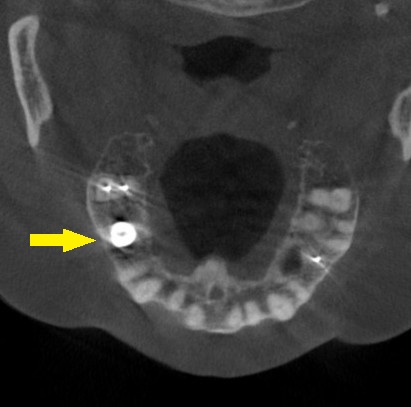

CTを撮影してみると、骨の高さが3mm程しかありませんでした。

これならと同意いただけましたので、本日、直径6mm、長さ7mmのインプラントを人工骨を用いることなく埋入しました。

下の写真、2段目が手術前、3段目が手術後のCTです。